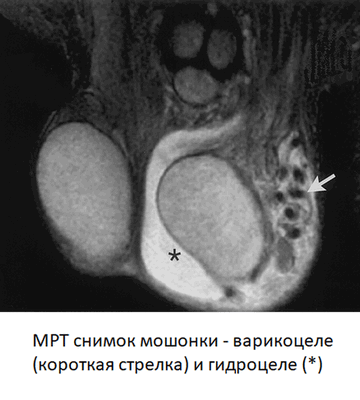

Варикоцеле (стрелка) и гидроцеле (*) слева.